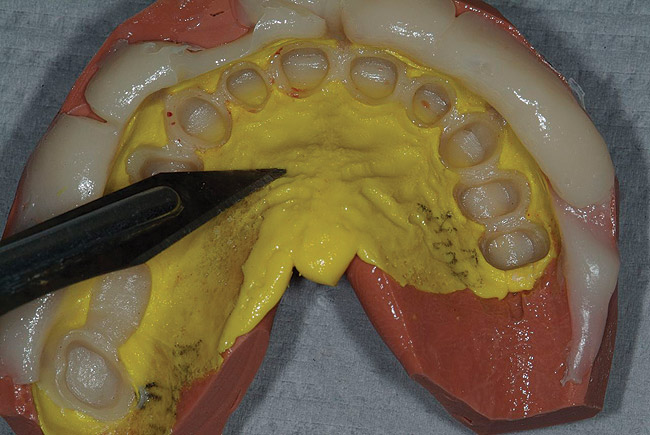

Figure 16  Bis-acryl provisional matrix. Deep notches are cut in the matrix for resin escape. Also note the notch in the midline for positioning.

Figure 16

Figure 17  Temphase escapes the matrix to the buccal, aiding in complete seating.

Figure 17

Figure 18  Minimal resin on palate demonstrates ideal matrix seating.

Figure 18

Figure 19  The Temphase tip is placed deep in the matrix and flow is directed around the arch to prevent bubbles in the embrasures and cusp tips.

Figure 19